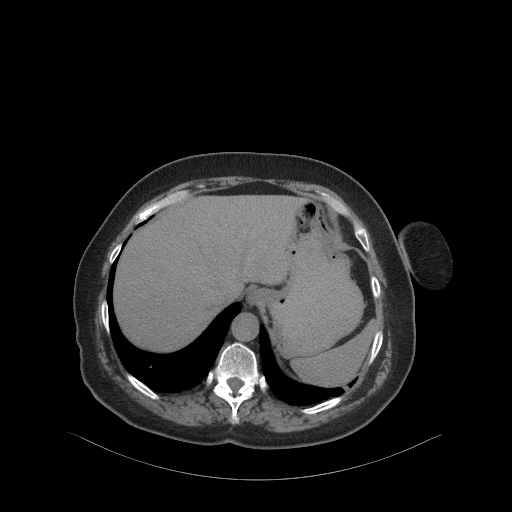

Generated VENOUS CT scan (A→B translation)

Full window (WL 1023.5, WW 4095 β†’ Low βˆ’1024, High +3071)